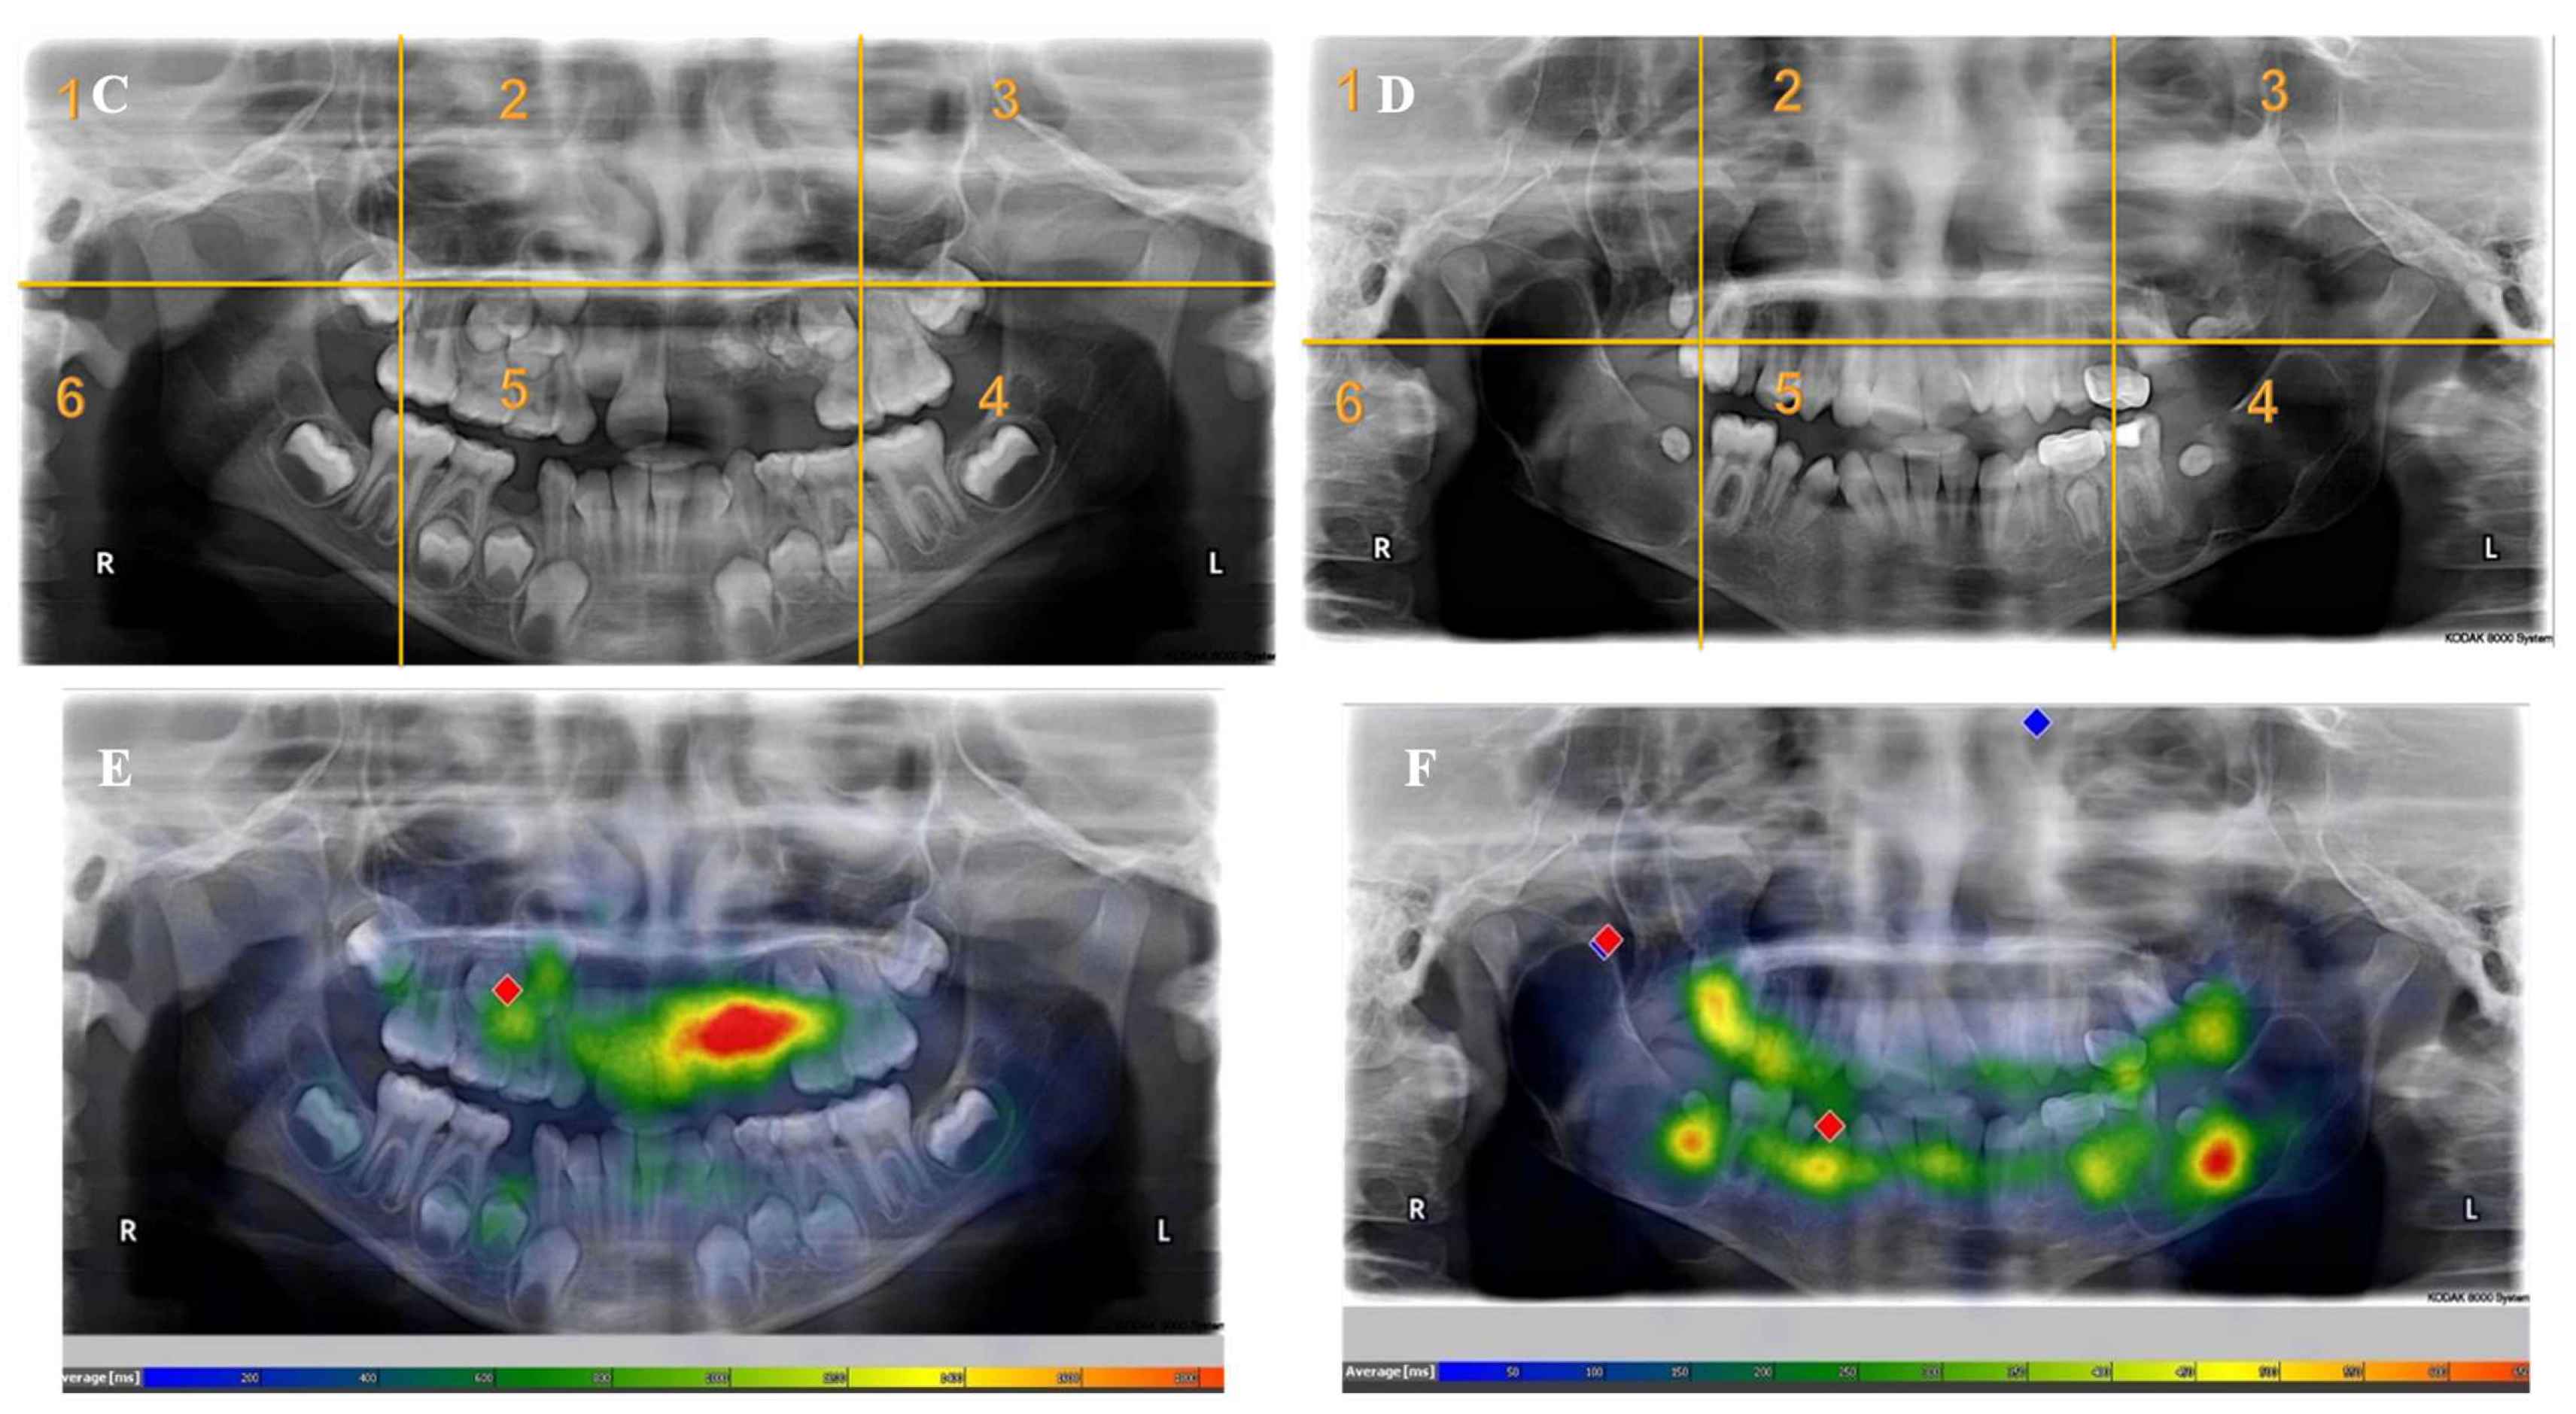

Appendix A. Radiographs Included in the Study

- Each panoramic radiograph displayed will be divided into sextants by yellow lines.